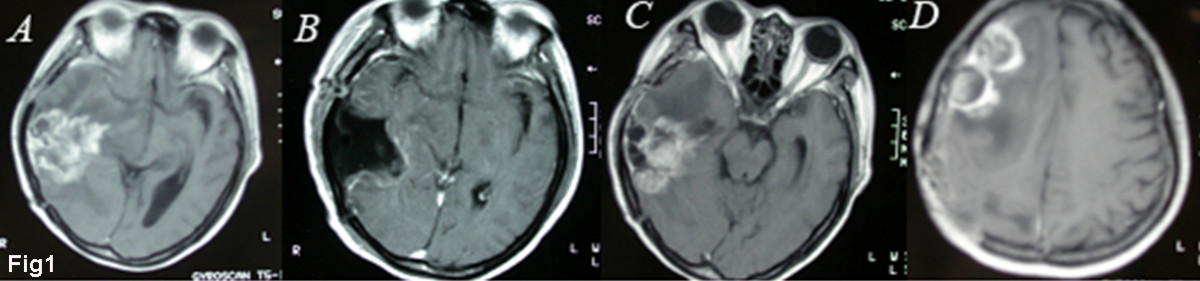

Our studies were approved by the Medical Review Board of Suzhou University Medical School. Signed informed consent was obtained from the patients or their legal guardians prior to sample acquisition. Fresh surgical specimens were obtained from a 52-year-old female patient who had undergone two operations with an interval of 6 months because of the rapid re-growth of tumor mass in the right temporal lobe. The patient had received one dose of radiotherapy (45 Gy) one month after the initial surgery, then three doses of chemotherapy (VM26 0.1 ivgtt × 3 days followed by MeCCNU 200 mg PO once) at one-month intervals. In recurrence, a new solitary focus emerged in the ipisilateral frontal lobe in addition to tumor re-growth in situ. The primary lesion was pathologically diagnosed as mixed glioma comprising anaplastic ependymoma and astrocytoma (WHO grade III), while the recurrent lesion had transformed and progressed into glioblastoma multiforme (WHO grade IV) (Fig. 1) despite the continuous post-surgical radiotherapy and chemotherapy.

Figure 1

MRI images of a 52-year-old female patient who underwent two operations with an interval of 6 months because of the rapid relapse of her tumor. A, The primary tumor located in the right temporal lobe and pathologically diagnosed as mixed glioma composed of anaplastic ependymoma and astrocytoma (WHO grade III). B, Post-operation image showing nearly total resection of the tumor. C, D, Relapse occurring 6 months later in situ and the ipsilateral frontal lobe; the recurrent lesion had transformed and progressed into glioblastoma multiforme (WHO grade IV).